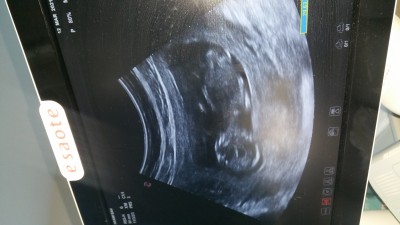

Cinsiyetini devlet hastanesine gittigim icin soylemiyorlar sizce nedir anneler :))

Erkek gibi gördüm sanki canim ya orda çıkıntı var sanki

Suan 15 haftalik cnm ama ordaki ultrsyon fotosu 2 hafta once cekildi